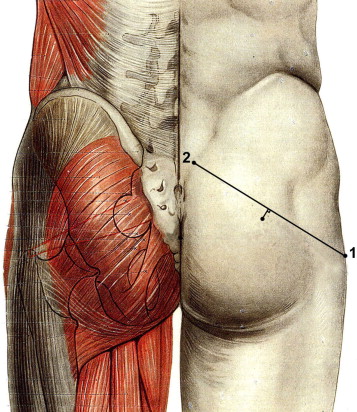

Анатомия мышц: Пириформис